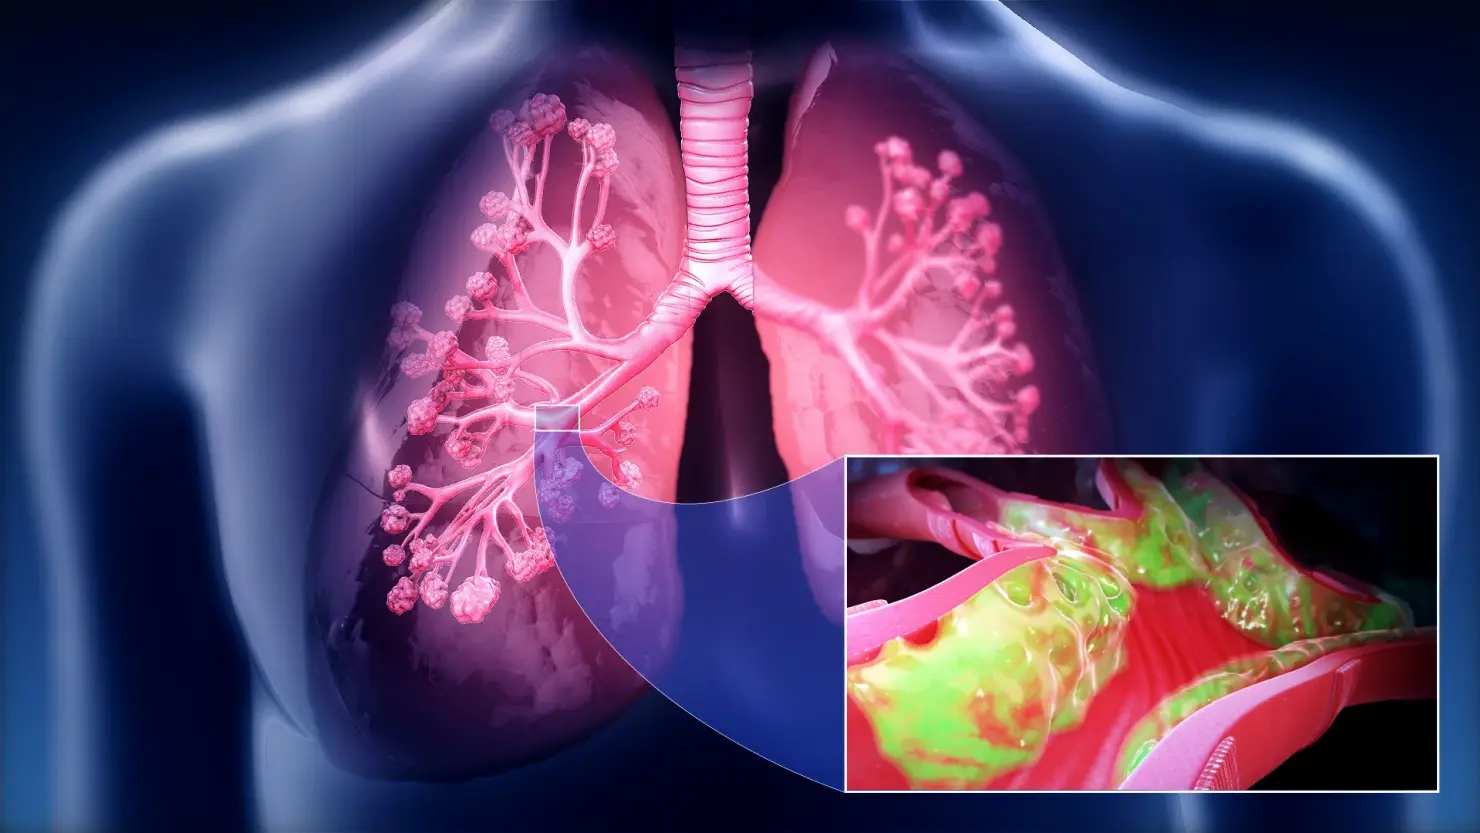

Routine tests miss the "respiratory evil" that Dr. Carson identifies in his functional medicine practice: A dense, hardened layer of old mucus and toxins (PM2.5, tar, heavy metals) that glues the air sacs (alveoli) shut.

"Inhalers only force the airways open for a few hours," Dr. Carson explains. "But in COPD patients, the Suffocation Layer is so thick that oxygen can't penetrate. It's like trying to breathe through a wet sponge coated in asphalt. This is why standard treatments fail."